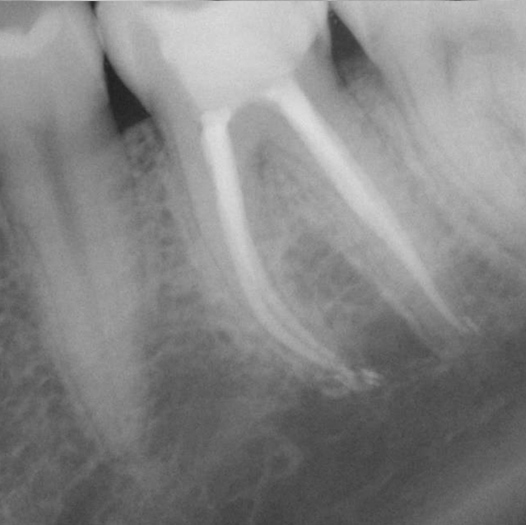

Before

After

Before Root Canal treatment

After Root Canal treatment